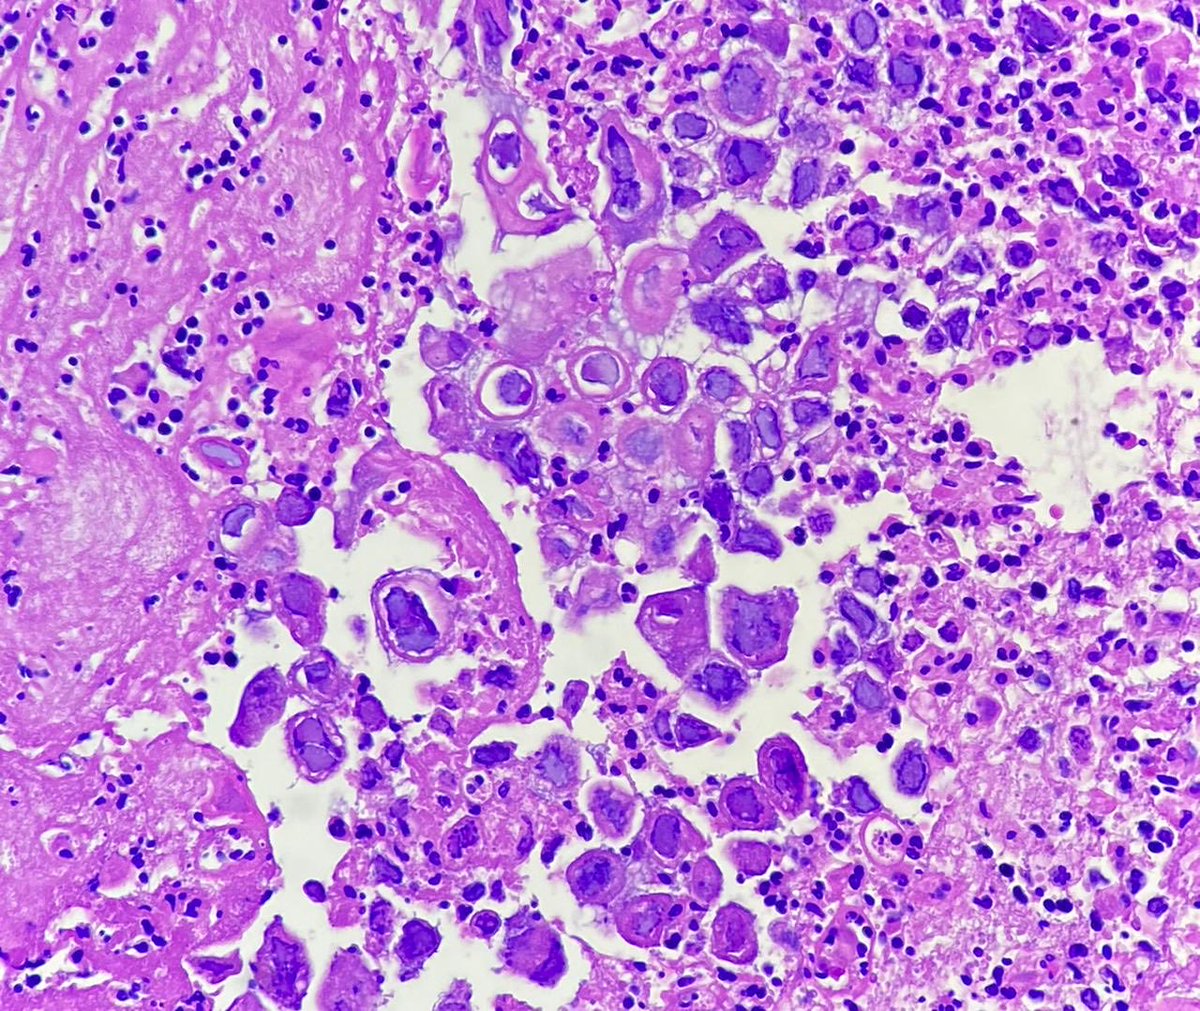

#hemepath #pathology #hematology So, a patient with CLL came in today, and these showed up!

redb56's tweet image. #hemepath #pathology #hematology So, a patient with CLL came in today, and these showed up!